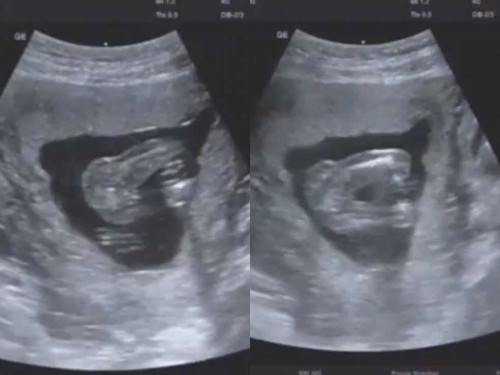

บ้านนี้16W หมอบอกยังเห็นเพศไม่ชัดเลยค่ะ 😅😅

เหมือนสาวน้อยเลยค่ะ เราได้สาวน้อยก็เป็นกลีบแบบนี้ รอหมอคอนเฟิร์มนะคะ